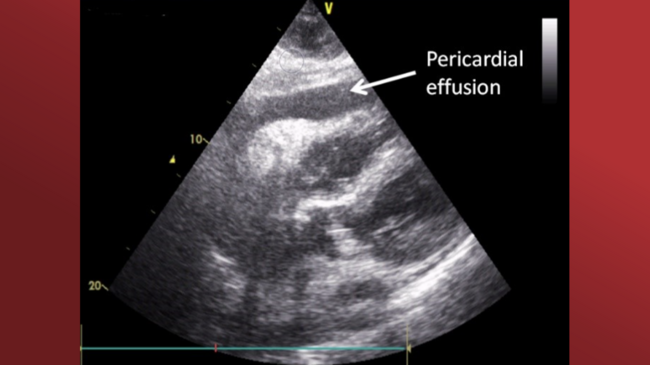

A 78-year-old male developed hemopericardium (Figure 1A) and hemodynamic collapse after an unsuccessful chronic total occlusion percutaneous coronary intervention (CTO-PCI). Echocardiographically-assisted emergent subxiphoid pericardiocentesis was performed, and a dual-lumen central-venous catheter (CVC) was inserted into the pericardial space. As matched allogeneic blood was not readily available and the patient was in pre-arrest condition, direct re-transfusion of aspirated intrapericardial blood served as a life-saving option.